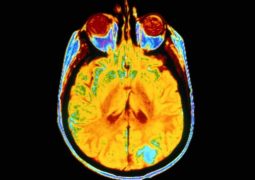

Milioni di persone soffrono di fibromialgia, una condizione che provoca dolore muscolo-scheletrico diffuso, disturbi del sonno, mal di testa ed alterazioni del tono dell’umore. La maggiorparte di questi ha molto lottato -o combatte ancora- per ottenere una diagnosi certa: allo stato attuale infatti non esistono test di laboratorio o altre indagini diagnostiche che identifichino con certezza tale condizione, senza contare che i suoi sintomi sono correlabili a numerose altre malattie. Un nuovo studio scientifico però potrebbe creare una svolta, grazie ad alcune immagini di risonanza magnetica.